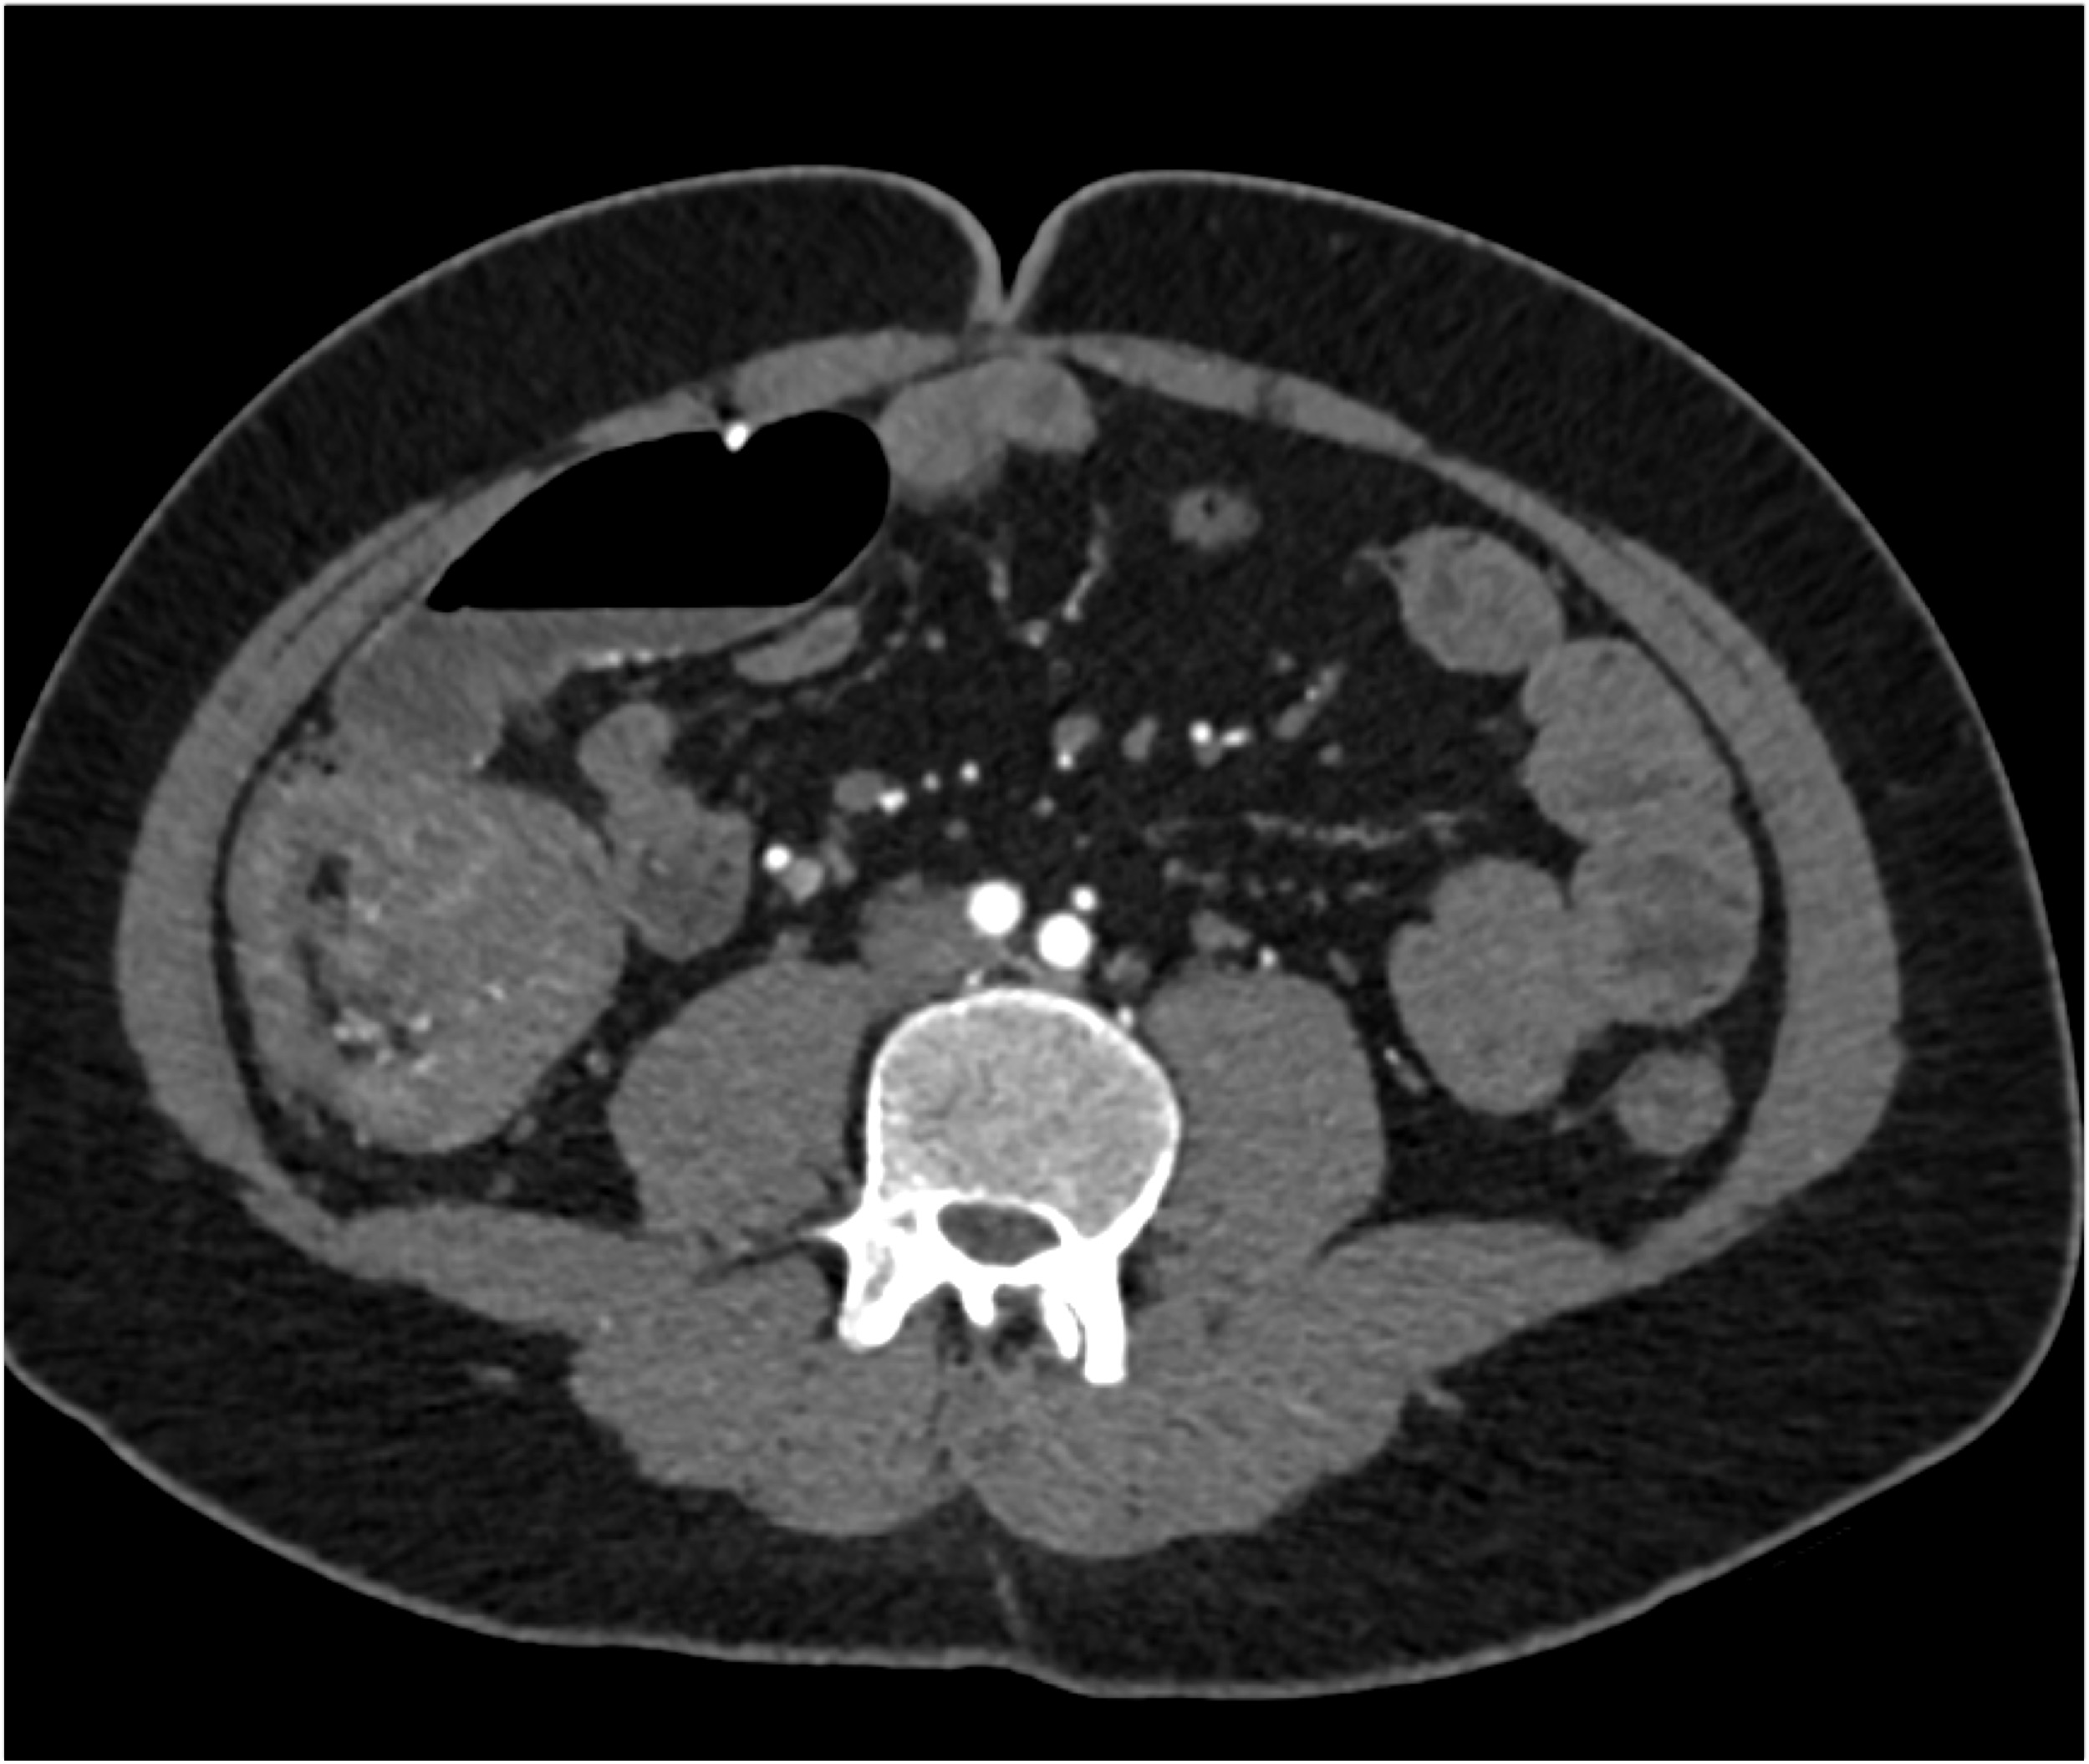

1) The most likely diagnosis in this case is?

lymphoma

Castleman disease

pheochromocytoma

paraganglioma